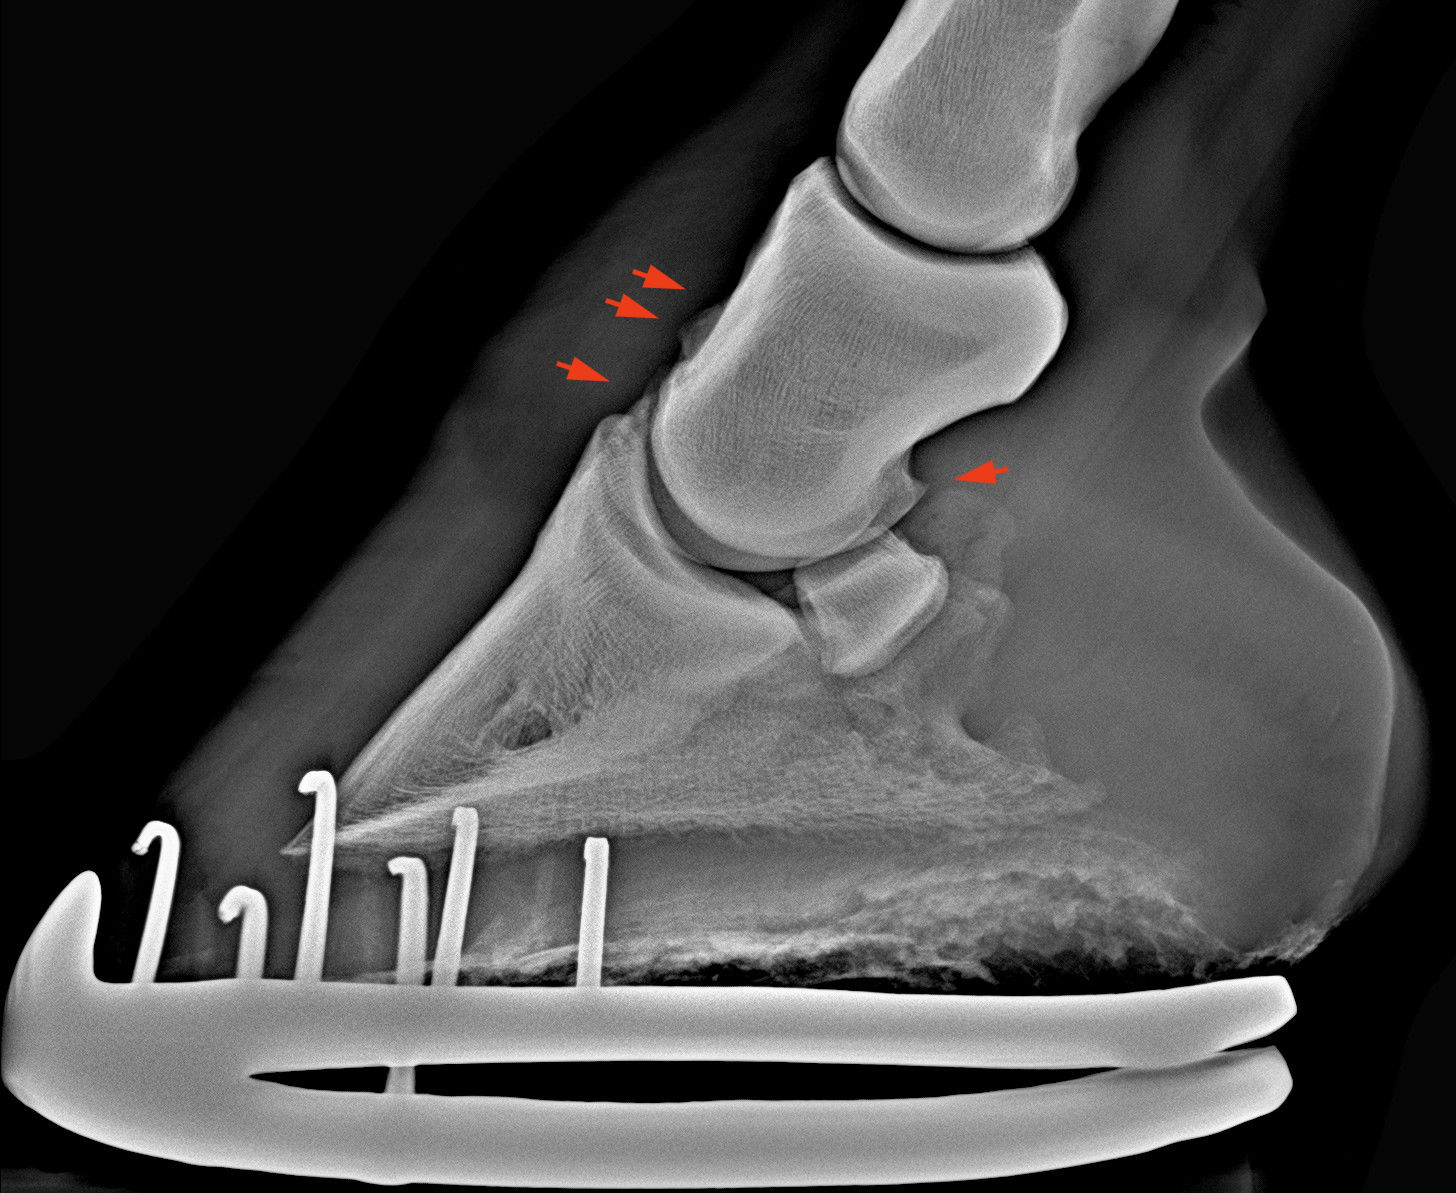

Enyhe RTG elváltozások. A nyilak csontfelrakódásokat mutatnak.